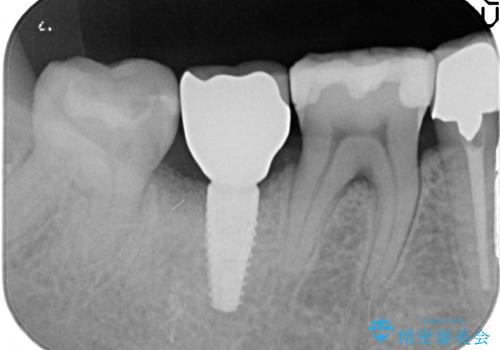

精査すると保存が難しいため抜歯をして、インプラントを埋入、かぶせ物を装着する計画としました。

インプラント治療により、周りの歯を削ることなく咬合を回復することができました。